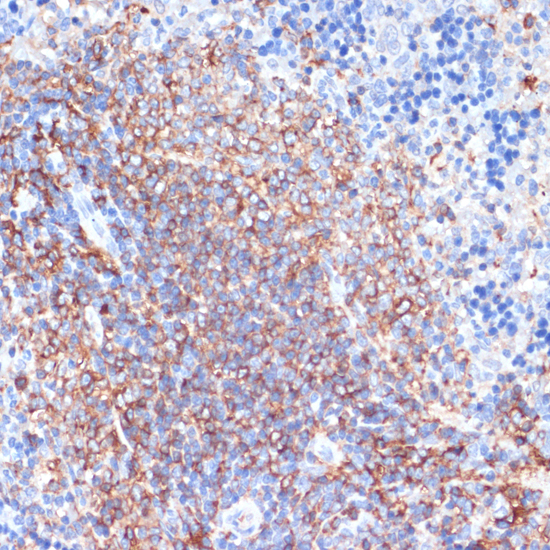

Immunohistochemistry - HLA-DRA Polyclonal Antibody

Immunohistochemistry of paraffin-embedded rat spleen using HLA-DRA antibody at dilution of 1:100 (40x lens).